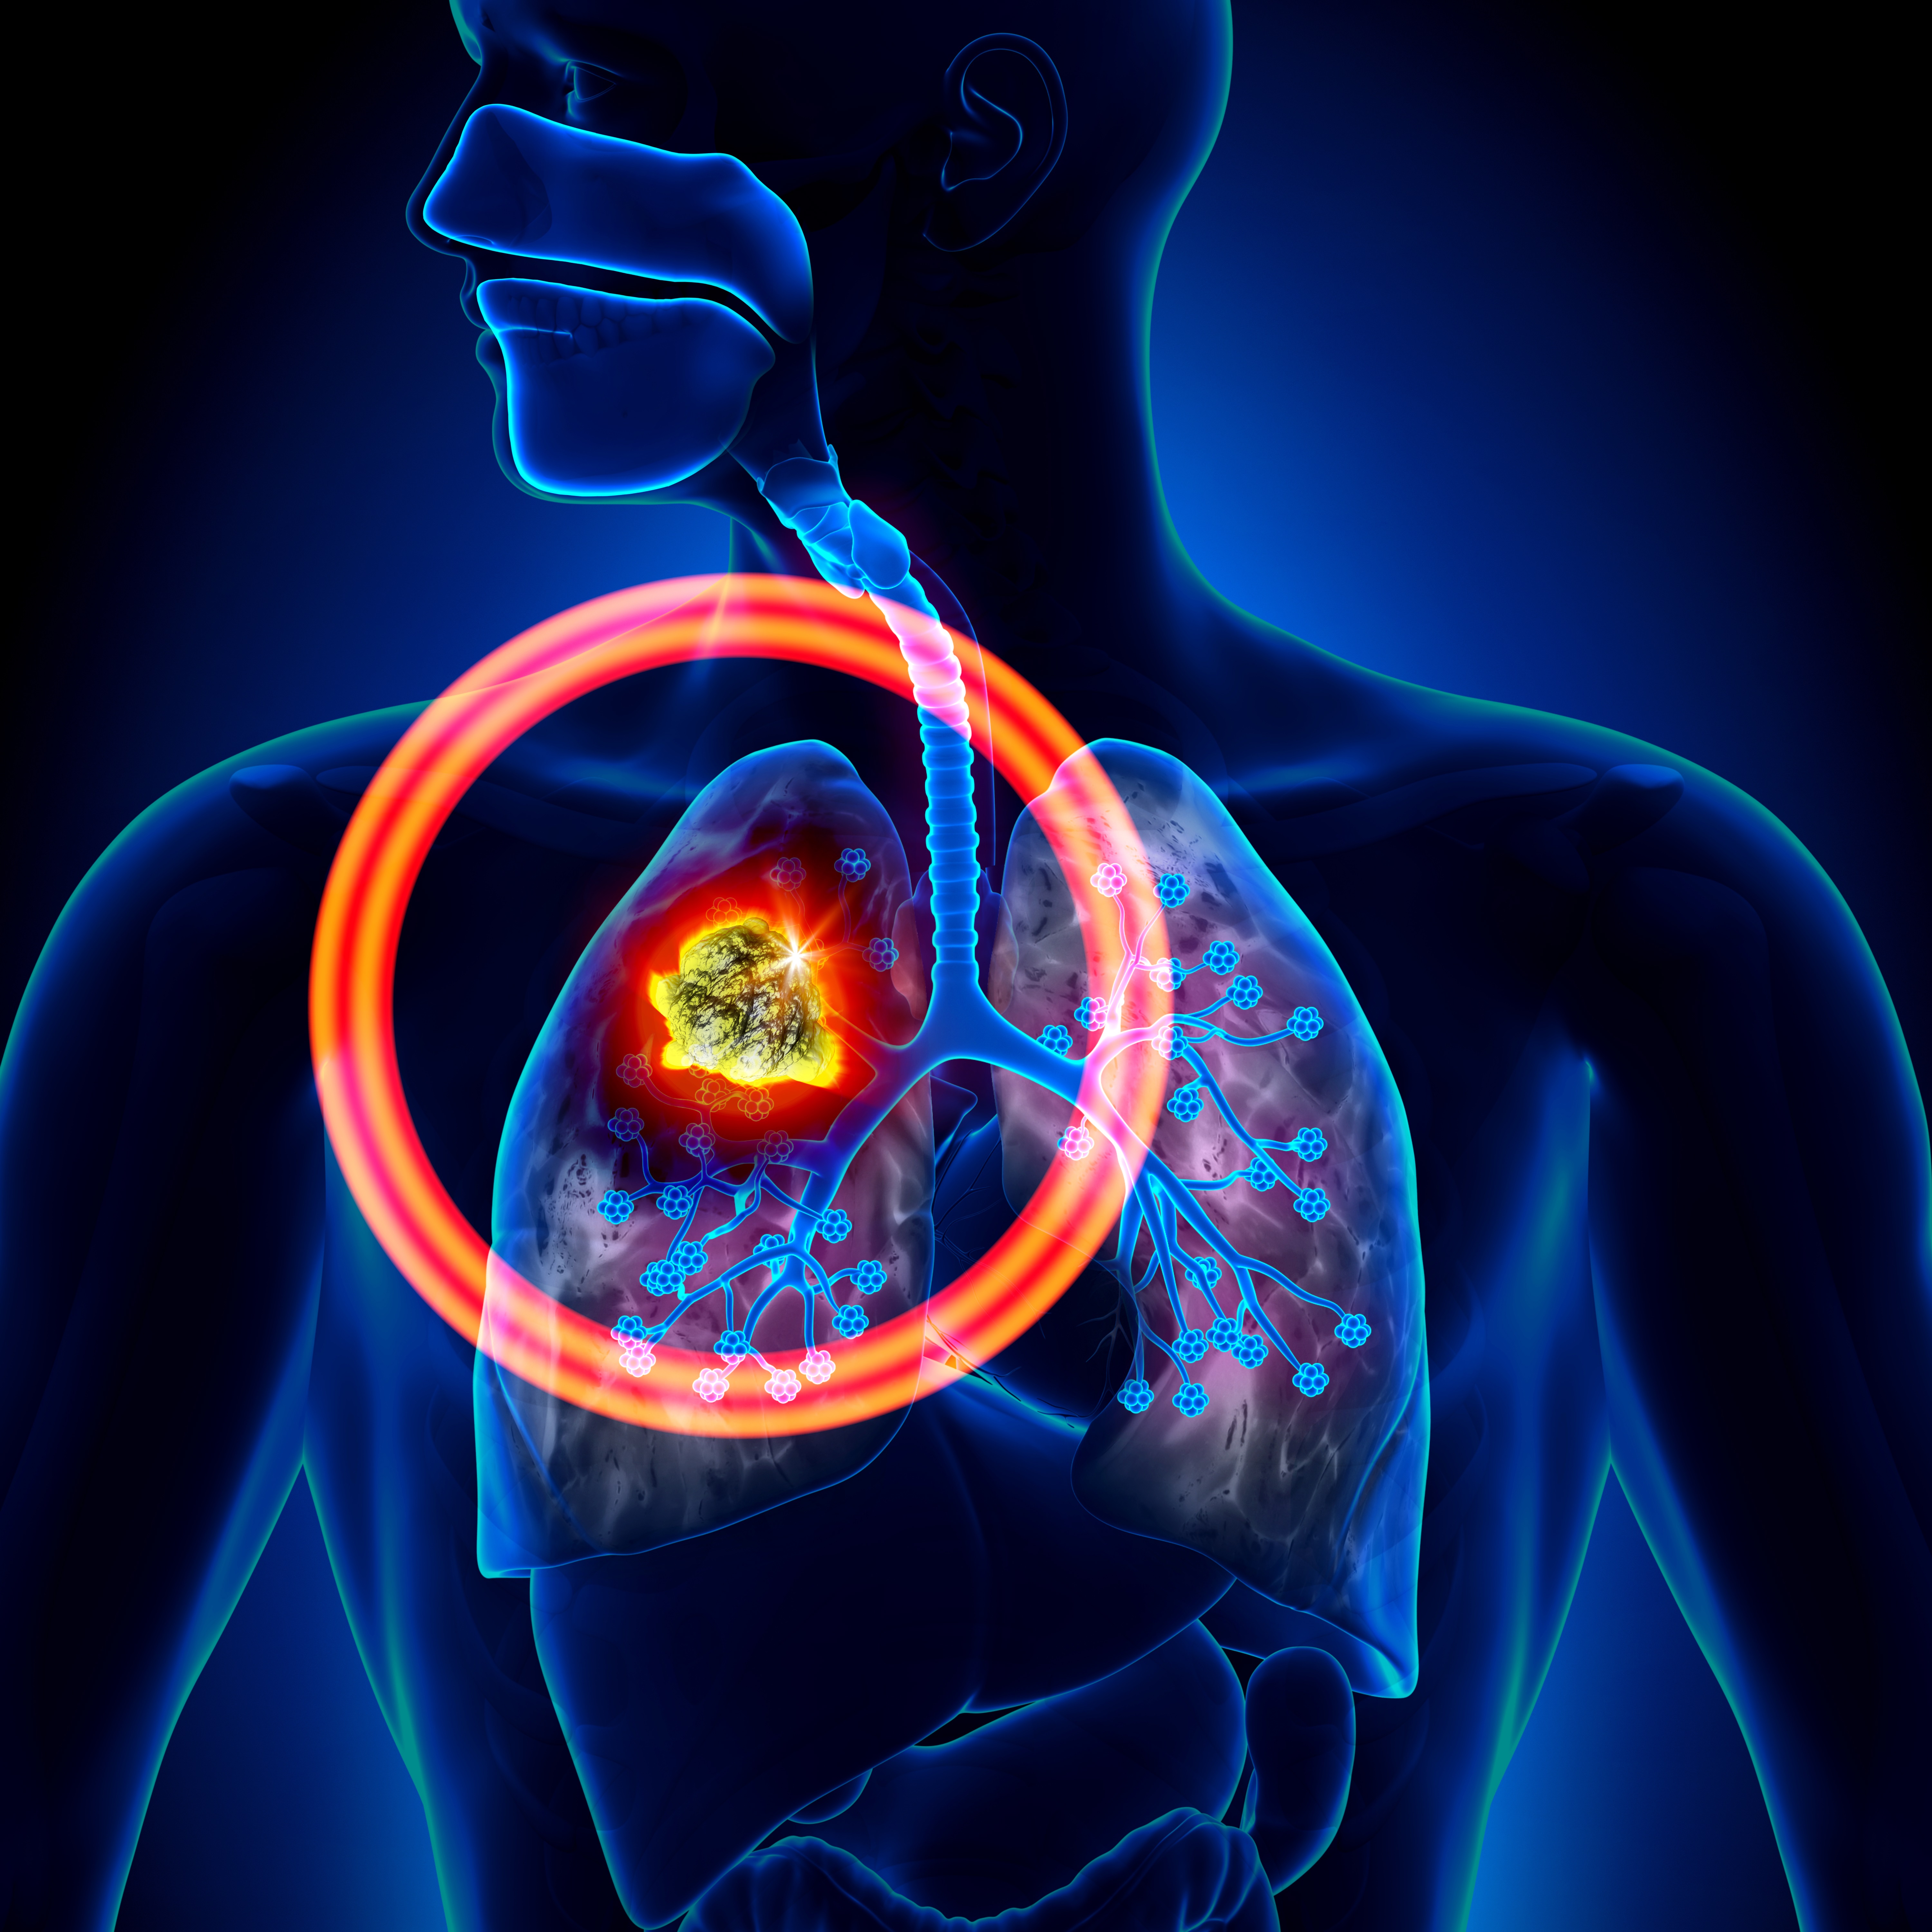

Pet Scan Cancer

PSMA PET-CT Accurately Detects Prostate Cancer Spread - NCI PET Scan: What It Is, Types, Purpose, Procedure & Results PET/MRI biomarkers guide personalized treatment for patients with pancreatic cancer - Mayo Clinic News Network PSMA-PET is rapidly changing the standard of care for prostate cancer patients | Pet Scan Cancer